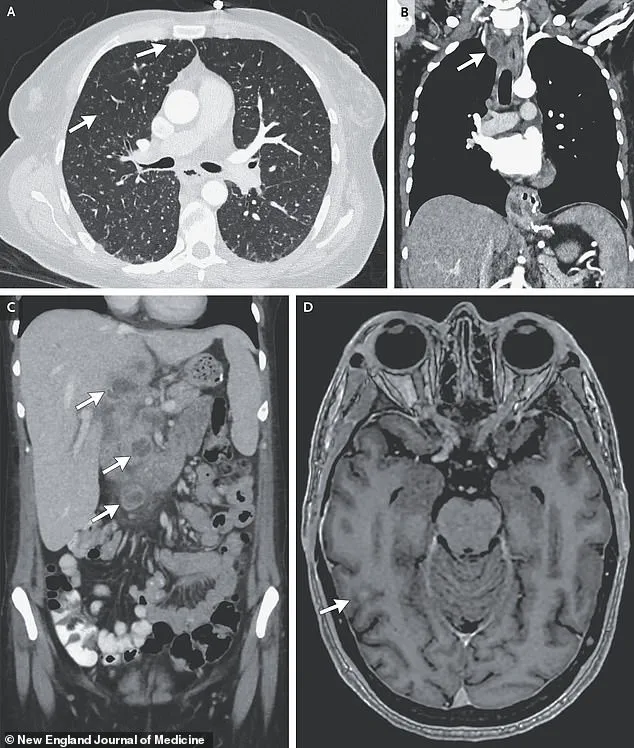

Further imaging and biopsies uncovered lesions in her liver, lymph nodes, pancreas, and brain—indications that the infection had spread far beyond the lungs.

Medical scans revealed nodules in her lungs, an enlarged lymph node, and lesions in her liver, pancreas, and brain—evidence of a TB infection that had spread far beyond its usual confines.